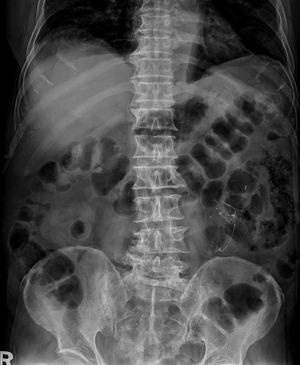

Pneumatosis Intestinalis

A 47-year-old male had sudden onset of massive bloody stool with negative result study of colon and stomach.